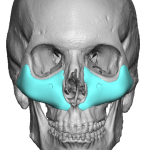

Otoplasty Reversal with ePTFE Postauricular Wedge Case Example

Reverse otoplasty refers to partially or fully undoing an overcorrected ear-pinning surgery so the ear sits a bit farther from the head again. While an overcorrected car from otoplasty surgery is ultimately determined by the patient there are some measurable guidelines for the natural angulation of the ear from the side of the head (auriculocephalic angle) When Read More…